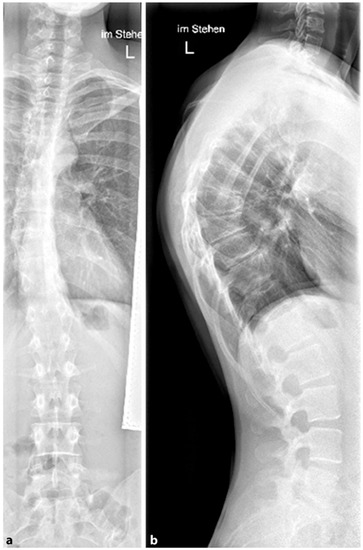

Figure 3. Patient post-Harrington instrumentation from T4 to L1 performed in 1980 (reprinted with permission [10]).

Growing rods are distraction-based systems that allow correction of the scoliotic spine in children and adolescents during growth. Since the first surgical techniques were described by Harrington in the 1960s (see Figure 3), with the goal of achieving spinal alignment by distraction without vertebral body fusion [42], there has been a significant evolution in the field of non-fusion techniques for scoliosis treatment. Because of this advancement, growing rods represent a standard procedure in the treatment of EOS. The idea behind TGRs is to straighten and realign the spine during growth by periodic lengthening of the instruments at least two times per year until completion of growth followed by definitive fusion [43].